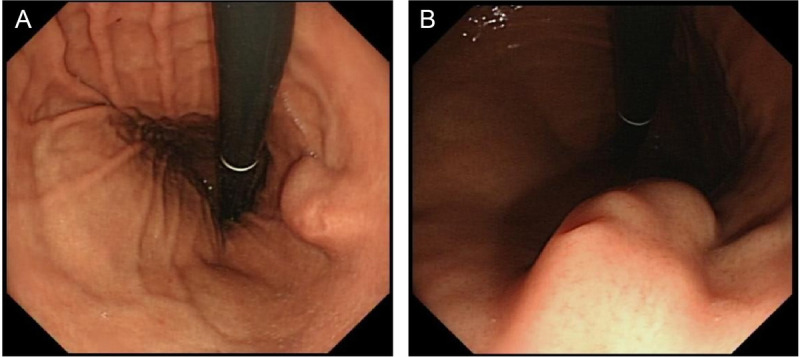

Intraductal papillary mucinous neoplasm originating from a heterotopic pancreas within the stomach.

起源于胃内异位胰腺的导管内乳头状粘液瘤。